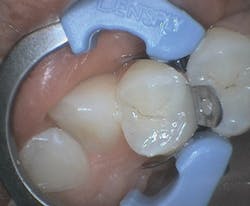

In another case, I used All-Bond Universal to fill a very typical Class II restoration for a female patient (figure 3). By this time, my assistant and I applied the bonding agent with ease and left the instruction sheet behind. Although I did not get to test All-Bond Universal's versatility with other procedures, I look forward to using it for indirect restorations in the future.

Figure 3: All-Bond Universal restoration